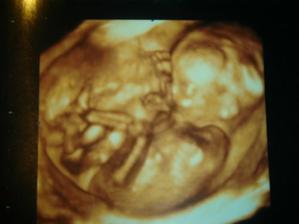

5/1/09 : 3D UTZ, opět potvrzena holčička, vážíme 510g. a měříme 25 cm.